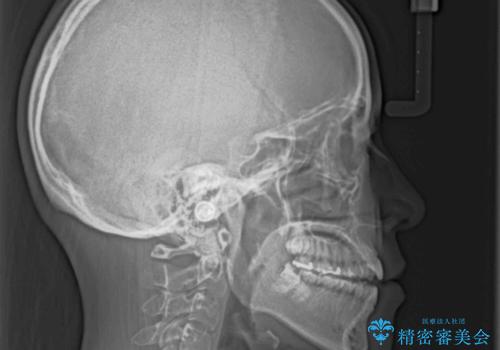

- 極端な開咬を気にして来院された患者様です。

開咬の方の特徴として、幼少期の指しゃぶりの癖や、強い舌の突出癖が挙げられます。

こちらの患者様も強い舌の突出癖が認められたため、矯正治療を行うにあたり、舌のトレーニングをしっかりと行っていただくように指示をいたしました。

開咬はインビザラインが得意とする歯列不正であるため、舌のトレーニングを行いながら、インビザラインにて矯正治療を行うこととしました。